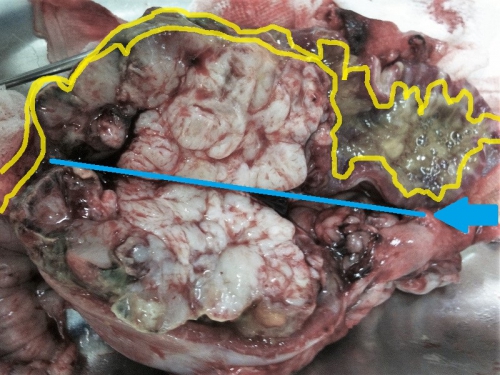

次の写真は摘出した腫瘤を青線に沿って縦方向に半分に切断した写真です。黄色の線で囲まれたエリアが小腸内腔で、消化された食事の通る管になっています。写真中央部、乳白色の腫瘤本体によって圧迫され、左側、2/3が狭窄(狭く絞られること)しているのがよく分かります。

この写真をご覧になって、消化された食事が小腸を通過するのが困難なのが想像できますでしょうか?かなり苦しかったであろうことは想像に難くありません。